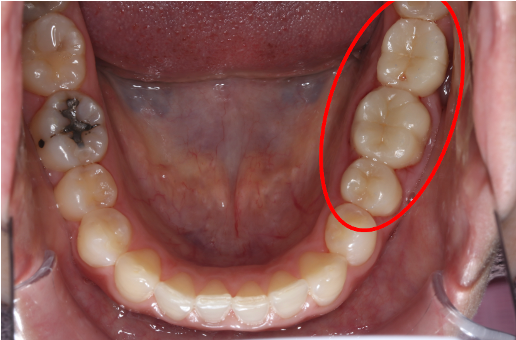

インプラント症例②

年齢 50代男性

治療期間 4ヶ月

インプラントメーカ ジンマーインプラント

治療内容 カスタムアバットメント、上部ジルコニア

治療箇所 左下6番

治療費用 380,000円